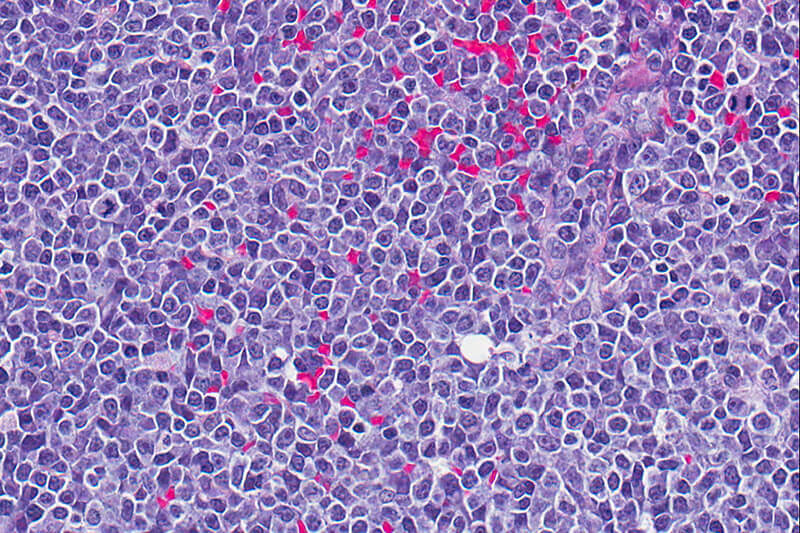

Tissue

A case for personalized medicine in the search for answers about cancer

Every three minutes, two people in the U.S. die from cancer. Some of the deaths related to the disease arise from the fact that the same drug that helps one person can be detrimental to another with the same type of cancer. “This is one of the strong cases for personalized medicine,” says Professor Nadia Atallah Lanman, who manages the Purdue University Collaborative Core for Cancer Bioinformatics.